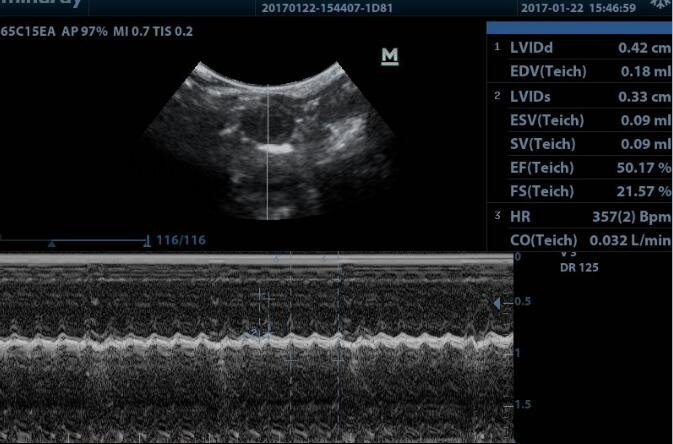

1. Cardiac function test: the changes of left ventricular end diastolic diameter (LVEDD), left ventricular end systolic diameter (LVEDS), ejection fraction (EF%) short axis shortening (FS%) were measured by echocardiography;